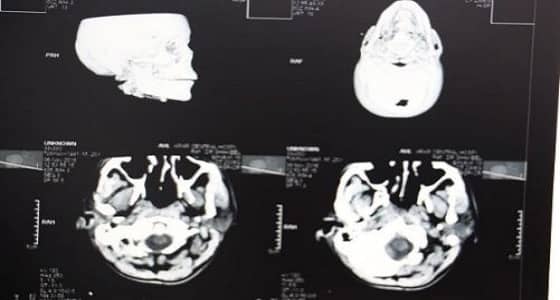

حمود الدهمشي

تمكّن فريق طبي بمستشفى عرعر المركزي من إنقاذ حياة مقيم إثر تعرضه لحالة دهس، حيث كان يعاني من إصابات متعددة انتفاخ واحتشاء نزفي شديد بالمخ ، كسر بالجمجمة والفك ، انحراف شديد للخط الناصف للمخ ، كسر بكامل القدم اليسرى.

وقام الفريق الطبي بقيادة استشاري جراحة المخ والأعصاب بإجراء عملية خزع جمجمة طارئ والاحتفاظ بجزء من عظم الجمجمة في جدار البطن، وذلك للسماح بتمدد أنسجة المخ خارج تجويف الجمجمة وتقليل الضغط داخل المخ حيث أثمرت نتائجها - بحمد الله -. وبعد استقرار حالة المريض تم إجراء العملية الثانية وهي تجميلية بالوجه للجهة المتضررة وبعد تحسن حالة المريض تم عمل العملية الجراحية الثالثة وإعادة تثبيت عظم الجمجمة في مكانه، وبعد أن تحسنت حالته الصحية تم السماح له بالخروج من المستشفى وهو بصحة جيدة ووضعه الصحي مستقر.